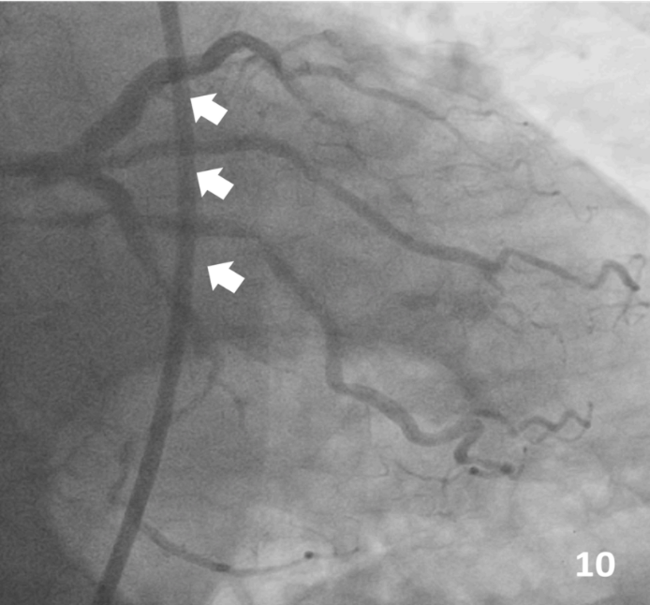

A 66-year-old male Jehovah’s Witness arrived at the emergency room having experienced typical persistent angina. Upon arrival, he was hemodynamically unstable. Electrocardiogram showed a high-risk pattern (Figure 1) and hs-cTn of 21 000 ng/L. Coronary angiography showed critical left distal main disease with trifurcation lesion to the left anterior descending artery (LAD), ramus intermedius, and left circumflex artery (LCx) (medina 1-1-1-1), and an 80% lesion in the middle segment of the LAD (Figure 2, 3).